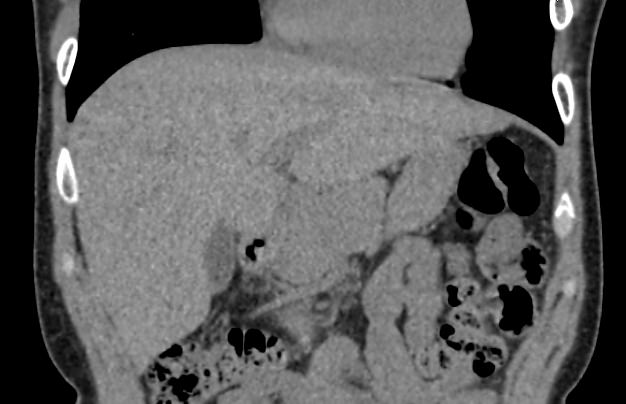

Печеночная ткань имеет обильное кровоснабжение, поэтому часто ультразвуковая диагностика заболеваний печени затруднена. Одним из наиболее информативных методов диагностики является мультиспиральная КТ печени, которая может проводиться в стандартном режиме и с внутривенным болюсным контрастированием. Введение йодсодержащего контрастного вещества значительно повышает диагностическую ценность компьютерной томографии и позволяет, в частности, выявить злокачественное образование на ранней стадии, отличить доброкачественный процесс от злокачественного, визуализировать изменения внутрипеченочных желчных протоков и многие другие патологические процессы.

Обследование печени посредством компьютерной томографии позволяет выявить следующие патологии:

- гепатоз различного генеза

- цирроз – разрастание соединительной ткани, которая замещает печеночные дольки;

- изменения воспалительного характера (гепатит);

- кисты;

- абсцессы;

- гемангиомы;

- первичные опухоли и метастазы;

- паразитарные заболевания (эхинококкоз, альвеококкоз)

- тромбоз сосудов печени.